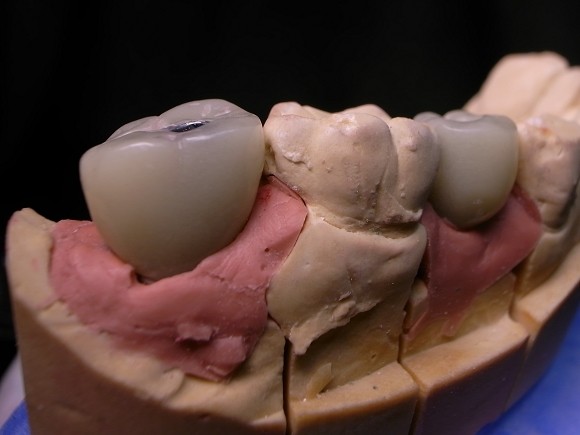

具有功能性與審美性的臨時假牙

#11.12.13 Bridge #21 Veneer

Cement retained

此外在Implant Treatment planning當中,

不只上半身的功能性與審美性,下半身牙肉軟組織的雕塑也不容忽視~

定出理想profile的位置

wax up

製作index ,確認abutment設計

Screw retained